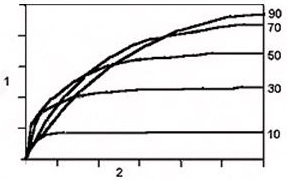

Figure 3. TR/T1 and Flip Angle Curve

Table 2. TR/T1 and Flip Angle Curve image legend Number 1 Signal in 0.2 increments 2 TR in 500 ms increments

- Flip angle: It affects the amount of recovery that occurs between each excitation pulse. As a general rule, the higher the flip angle the more saturation and T1 effects are seen in the image.

- TR and Flip angle: 2D sequential or 3D mode: keep the TR and flip angle within 10 points of one another to produce the optimum SNR.